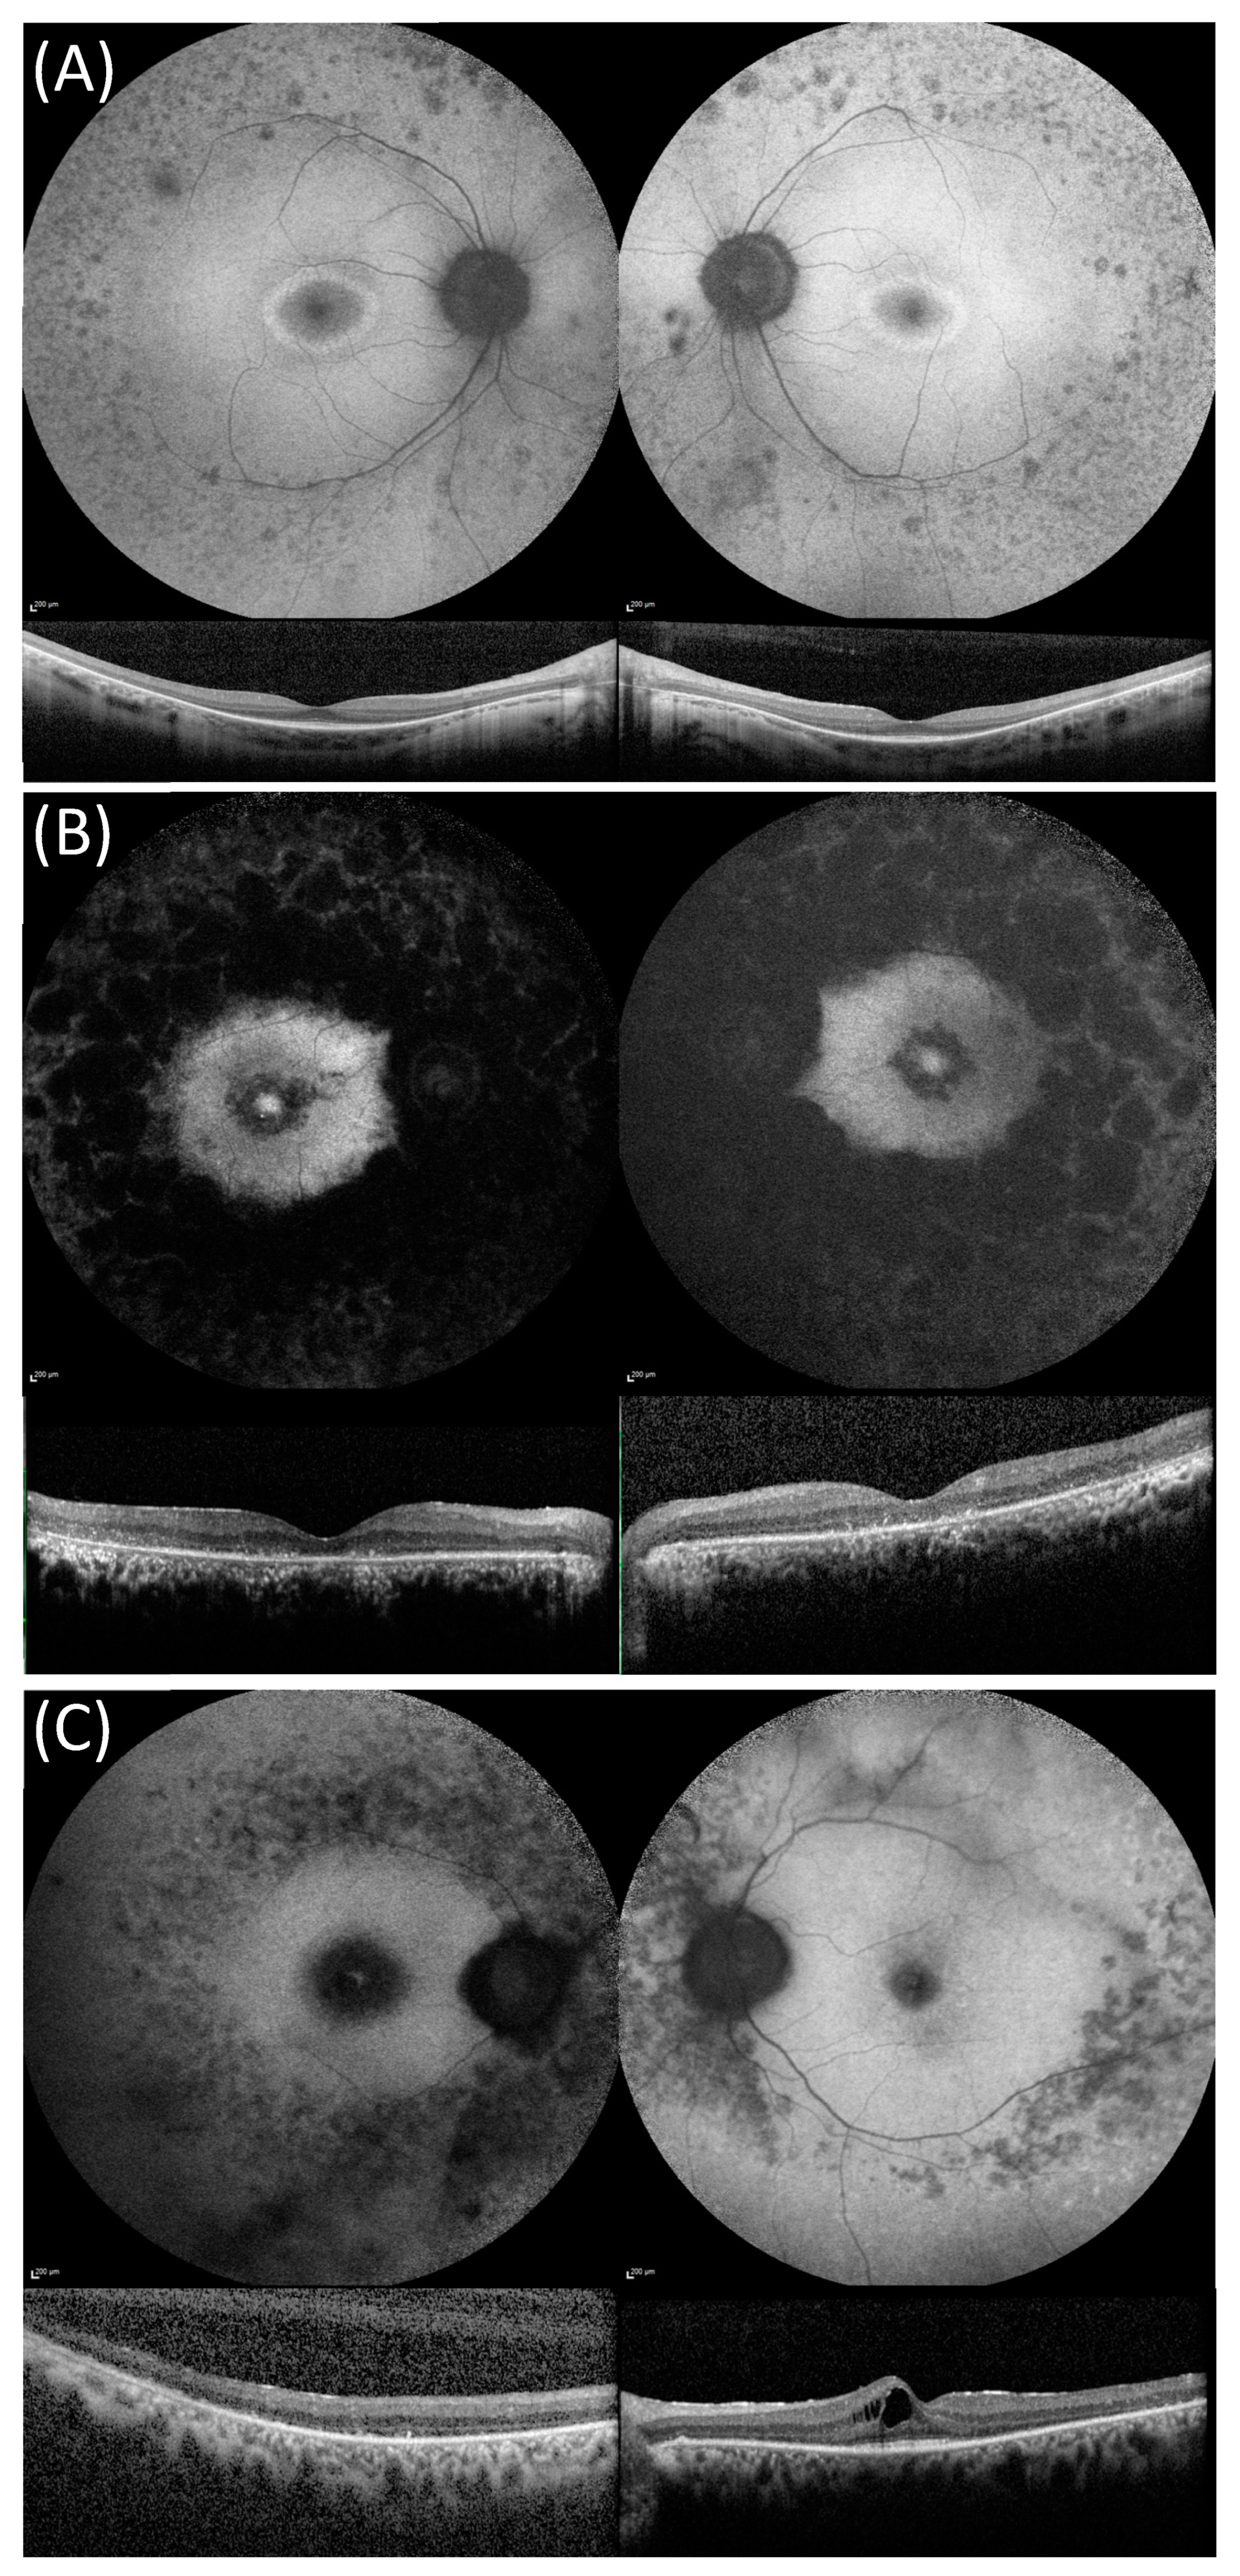

| FAF pattern * | n = 22 | n = 25 | |||

| Hyperautofluorescent ring | 12 (54.6%) | 18 (72.0%) | 0.040 | ||

| Hyperautofluorescent foveal patch | 9 (40.9%) | 3 (12.0%) | |||

| Foveal atrophy | 0 | 2 (8.0%) | |||

| OCT findings | |||||

| CMO | 8 (38.1%) | 21 | 1 (4.8%) | 21 | 0.021 |